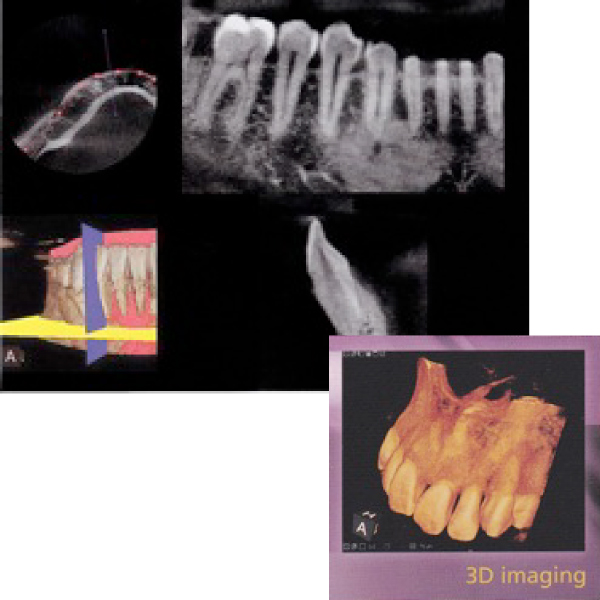

• CT診断・最新の歯科用3D

• CT(低線量)を用いたきめ細やかな診断を行います。(インプラント治療以外は、別途料金3000円~がかかります。)